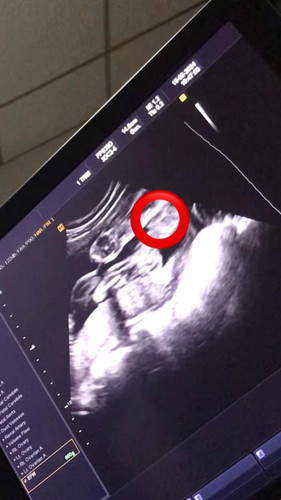

เเม่ๆช่วยดูหน่อยค่ะเเบบนี้ เพศ ญ หรือ ช ค่ะ 27 สัปดาห์เเล้วยังไม่ทราบเพศลูกเลยค่ะ

เพศหญิงน้องจะเปนแบบนี้นะคะแม่ (รุปขวามือ)